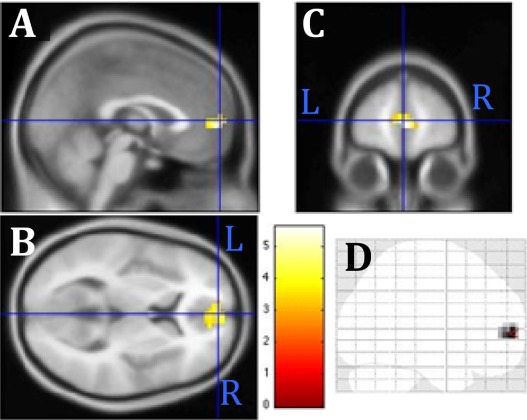

Activity of the medial prefrontal cortex after psycho-spiritual healing (Baldwin et al., 2016).

2 These Bad Memory/Feeling blocks were also compared to Neutral Memory/Feeling blocks that evoked memories and feelings about a neutral topic (e.g., the weather). This is the pre/post contrast shown in the first figure of the post.